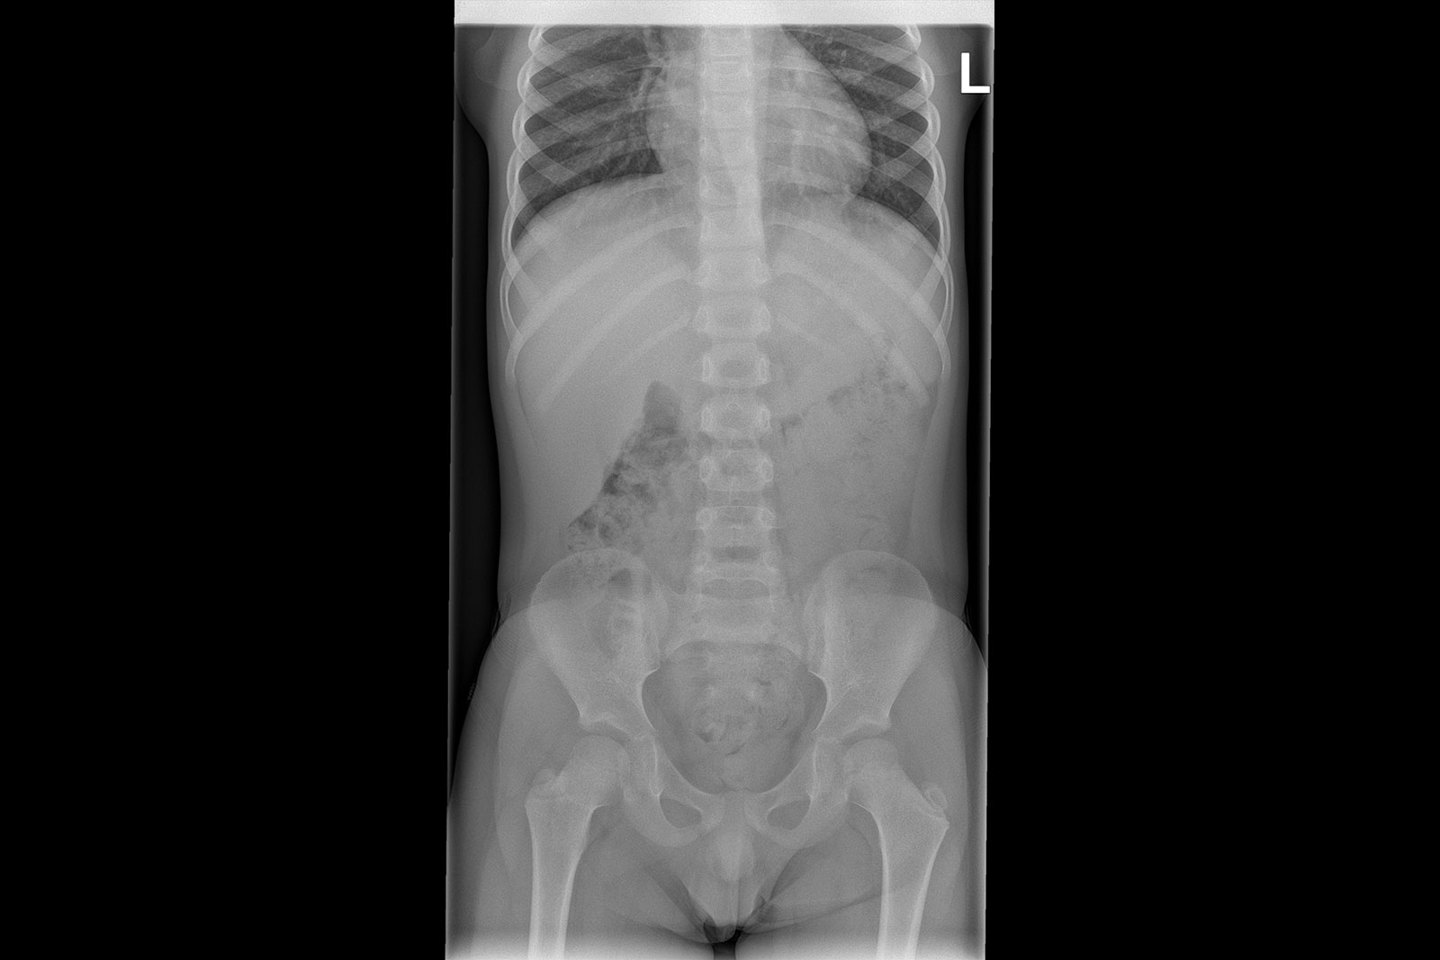

Zo ziet een foto van de binnenkant van je buik eruit.

This is what a picture of the inside of an abdomen looks like.

Voici comment se présente une radio de l’intérieur du ventre.

Tak wygląda zdjęcie wnętrza brzucha.

Bu, bir karın içi fotoğrafının nasıl gözüktüğüdür.

هكذا تبدو صورة ما بداخل البطن.